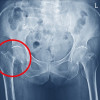

Fraktur Femur

Data epidemiologi memperkirakan terdapat sekitar 10-21 kasus per 100.000 orang tahun untuk fraktur femur pada shaft. Kejadian pada pria tertinggi pada kelompok usia 15-35 tahun. Sedangkan pada wanita, kejadian fraktur femur tertinggi pada usia di atas 60 tahun.[2]

Insiden fraktur femur pada shaft di seluruh dunia berkisar antara 10-21 per 100.000 per tahun. Sebanyak 2% dari kasus tersebut merupakan fraktur terbuka. Distribusi berdasarkan usia pada pria dilaporkan tertinggi pada kelompok 15 hingga 35 tahun, sedangkan pada wanita di usia 60 tahun ke atas.

Mekanisme fraktur pada pria yang tersering adalah kecelakaan mobil atau mekanisme energi tinggi lainnya. Mekanisme pada wanita yang tersering adalah jatuh.

Pada kelompok usia lebih muda, mekanisme energi tinggi merupakan yang paling banyak terlibat. Di sisi lain, pada lansia fraktur femur sering berkaitan osteoporosis.[2]

Pada anak, fraktur femur pada shaft berkontribusi sebesar 0,7-1,7% dari keseluruhan fraktur pediatrik. Angka tersebut merupakan 3,5% dari keseluruhan fraktur tulang panjang ekstremitas pada anak.[11]